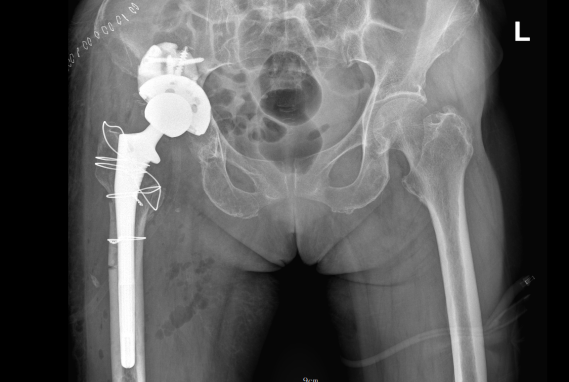

术后

经过系统围手术期调理治疗,患者血红蛋白及白蛋白明显升高,基础病控制良好,可以耐受手术。在pilipili 骨科团队三小时的不懈努力下,丁阿姨的手术取得了圆满成功,目前术后三周已康复出院,髋关节疼痛明显缓解,关节功能逐渐恢复,已开始部分负重行走。